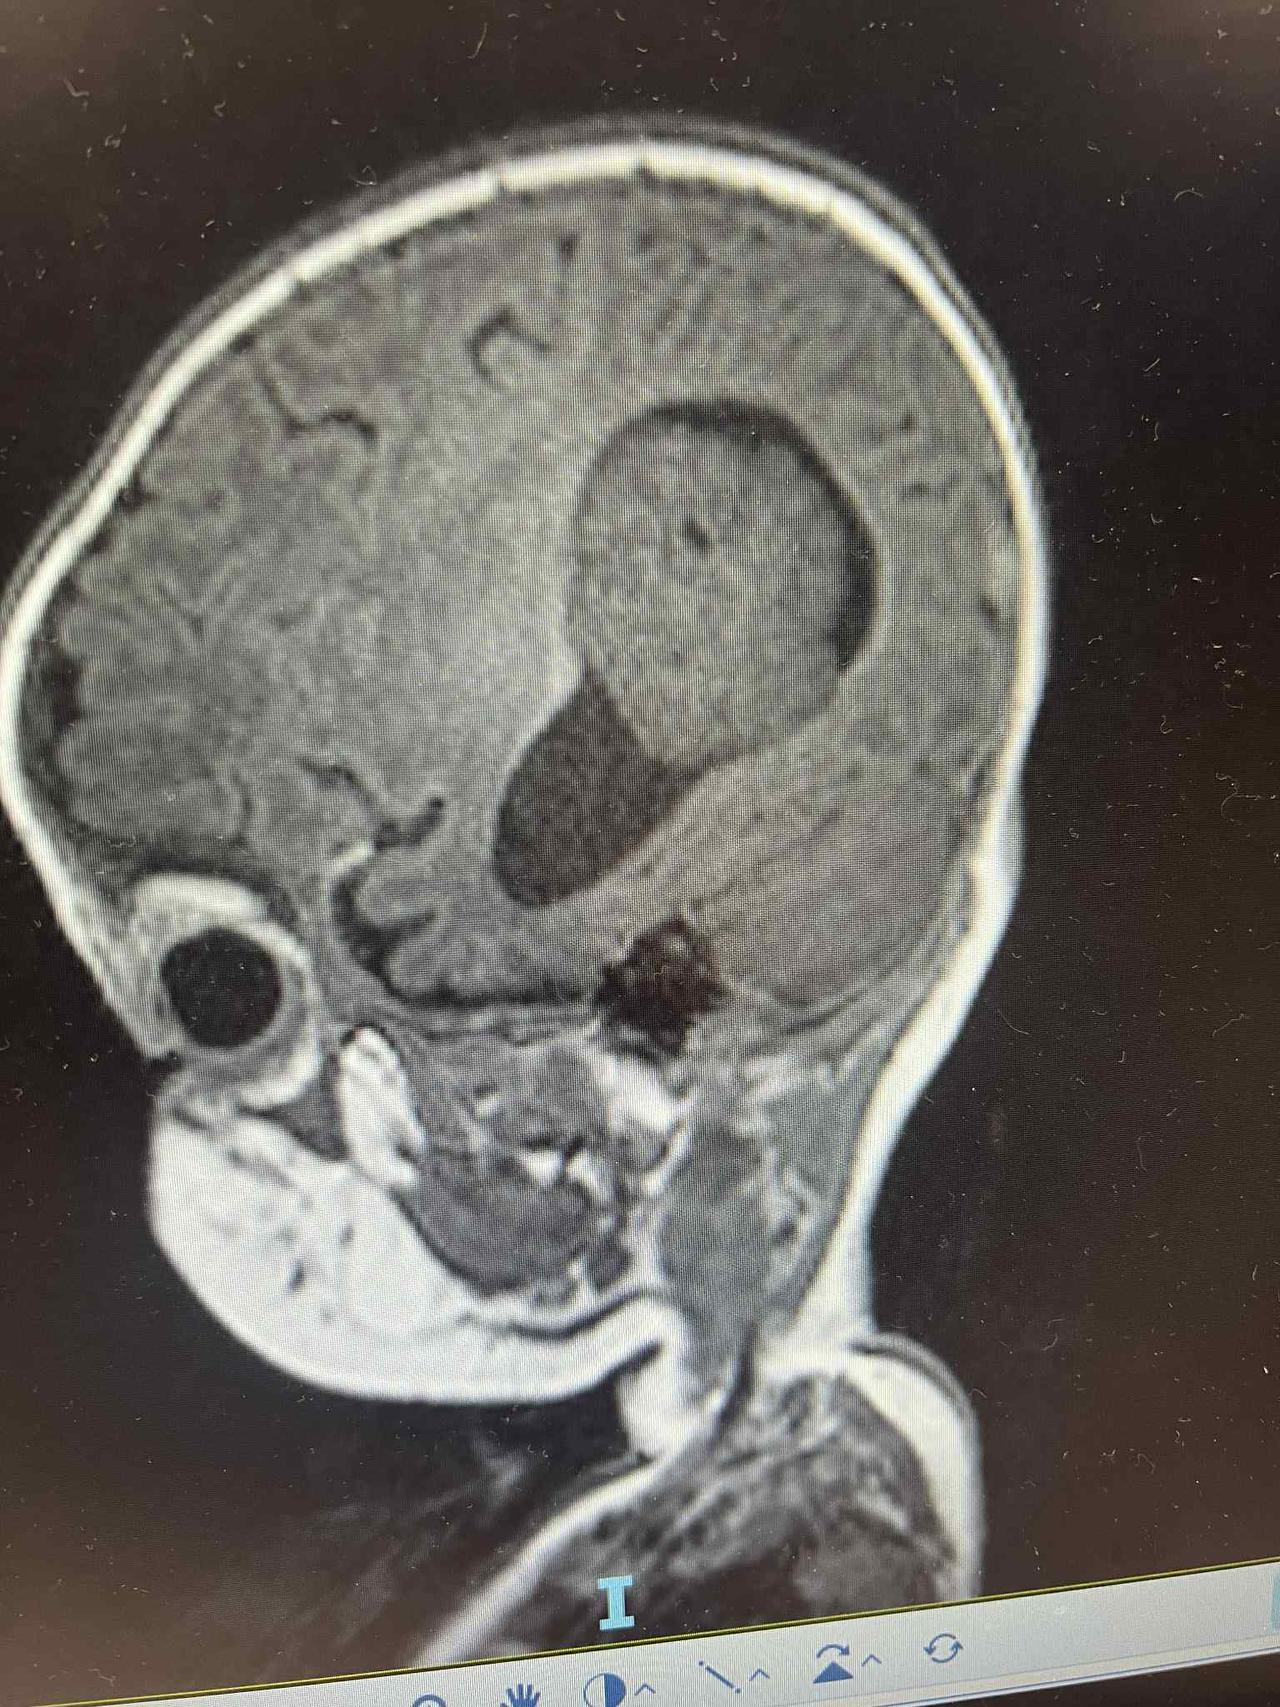

This handsome brave boy is 6 months old now and has successfully recovered from his big 9 hour surgery, which was first to stop the blood flow feeding the tumour followed by the surgery to remove the full tumour successfully. Unfortunately after the shunt was put in and a round of chemo was given to Baby Declan it showed the tumour had grown quite quickly so the urgency to remove the tumour came around quicker than we expected.

The very rare tumour Declan has was an Atypical choroid plexus papilloma we are still waiting on more tests to confirm and discuss the next steps.

Declan had his MRI post Chemo down in Wellington on the 9th December and unfortunately the chemo has not shrunk the tumour at all in fact it has grown we are heart broken 💔 Declan and his Dad have flown back to starship today and I will be driving up tomorrow (Sunday) as they are proceeding with the surgery Monday the 15th where they are hoping to remove the tumour safely but do a procedure before hand to stop the blood flow feeding the tumour. There are so many risks that we have been informed about re the surgery and we are really hoping for a positive outcome so please keep Baby Declan in your thoughts and Thank you to each and every one of you who have donated to help through this unfair time 🥹

Declan had 1 of his first surgeries and that was putting a shunt in so they can drain the excess fluid from his brain to his abdomen as removing the tumor isnt the best thing to do atm as he is still so tiny and would be life threating!

While the oncologist, surgical nurse and specialist came together they said the are concerned about a few bits the lit up in Declan's MRI, they suspect cancer.